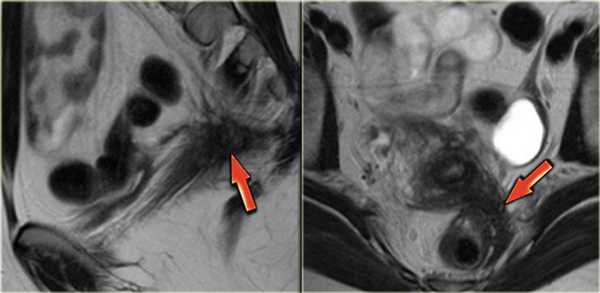

Покажет ли МРТ эндометриоз? На Т2 взвешенных сагиттальных МР-томограммах визуализируются два патологических веерообразных участка, дающих гипоинтенсивный сигнал (красные стрелки). Эти изменения типичны для эндометриоза с инфильтрацией стенки кишечника. Также определяется подслизистый отек, характеризующийся гиперинтенсивным сигналом со стороны отделов стенки кишки, расположенных ближе к просвету